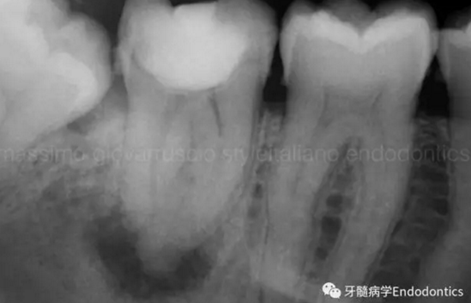

圖9.當(dāng)遇到了根尖方向的阻力,退出銼,使用銼預(yù)彎鉗(Endobender)平滑的預(yù)彎銼尖部的2mm,將銼上的硅膠止動(dòng)片的方向指示調(diào)成朝向銼彎曲的方向,這樣你就可以繞過障礙形成通路了。

圖10.探查時(shí)小心地使用給手表上發(fā)條的動(dòng)作使銼向前通過障礙。遇到阻礙時(shí),稍微回拉銼,將銼尖轉(zhuǎn)向新的方向,向根尖方向扭動(dòng),觀察銼是否前進(jìn)。如果沒有,將銼回拉,重新將彎曲的銼尖改變方向,觀察是否通過。不斷重復(fù),觀察是否前進(jìn),直至通路形成。必須使用根測(cè)儀和X線片檢查在障礙通過后是否到達(dá)了根尖止點(diǎn)。

圖11.術(shù)后X片顯示完成了根管的三維充填并很好地保留了復(fù)雜的解剖形態(tài)結(jié)構(gòu)。

圖12.對(duì)于較為困難的病例,探查根管時(shí)可能需要很多嘗試。一旦銼的尖部繞過了阻礙,會(huì)深入根管。